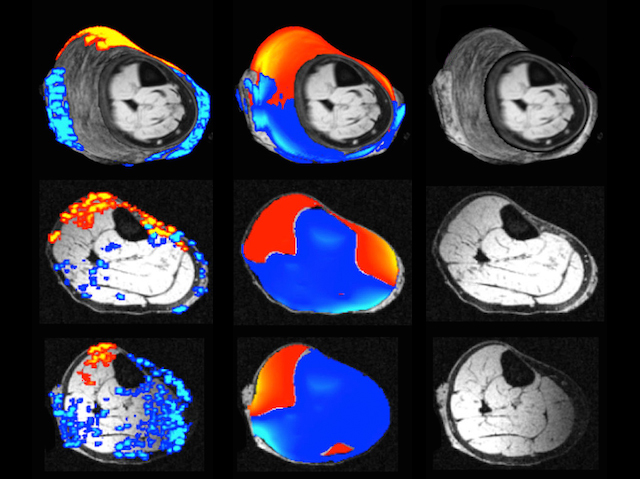

Zapping a patient’s brain with electrical current might sound like an extreme way of improving their mental health. But transcranial direct current stimulation (tDCS) involves gently guiding or 'modulating' brain activity. Using a human thigh here, rather than a brain, researchers test a new method to keep an eye on tDCS treatments in real time. Magnetic resonance imaging (MRI) scanners pick up on tiny changes to invisible magnetic fields caused by the electrical current – revealing different patterns overlaid in orange and blue (middle) on an MRI slice (right) through the thigh. The relationship between current and magnetism is so predictable that tDCS can even be simulated with a computer model (left). Using MRI to monitor tDCS will help in targeting treatments more precisely when tackling psychiatric disorders like drug addiction and depression.